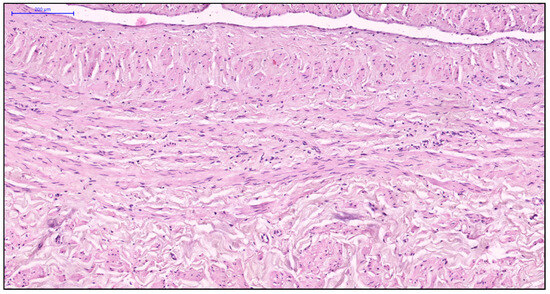

Effects of Two Decellularization Protocols on the Mechanical Behavior and Structural Properties of the Human Urethra

by Marcela Kuniakova, Zuzana Varchulova Novakova, Daniel Haspinger, Justyna Anna Niestrawska, Martin Klein, Paulina Galfiova, Jan Kovac, Michal Palkovic, Lubos Danisovic, Niels Hammer and Stanislav Ziaran

Int. J. Mol. Sci. 2024, 25(22), 12361; https://doi.org/10.3390/ijms252212361 - 18 Nov 2024

This study evaluates the effects of two decellularization protocols, enzyme-detergent (ED) and detergent-detergent (DD), on the structural and biomechanical properties of human urethral tissue. Urethral samples from 18 individuals were divided into ED (n = 7) and DD (n = 11) [...] Read more.

This study evaluates the effects of two decellularization protocols, enzyme-detergent (ED) and detergent-detergent (DD), on the structural and biomechanical properties of human urethral tissue. Urethral samples from 18 individuals were divided into ED (n = 7) and DD (n = 11) groups, with native samples (n = 3) serving as controls. Histological and ultrastructural analyses confirmed that both protocols effectively removed cellular content while preserving essential extracellular matrix (ECM) elements, such as collagen and elastic fibers. Immunohistochemical staining for collagen IV and fibronectin revealed no significant differences between decellularized and native tissues, indicating intact ECM structure. Biomechanical testing demonstrated that DD-treated tissues had significantly lower Cauchy stress (1494.8 ± 518.4 kPa) when compared to native tissues (2439.7 ± 578.7 kPa, p = 0.013), while ED-treated tissues were similar to both groups. Both decellularized groups exhibited reduced stretch at failure and elastic modulus compared to native tissues. Cytotoxicity assays using adipose-derived stem cells demonstrated no signs of toxicity in either protocol. Overall, both ED and DD protocols effectively preserved the urethral ECM structure and mechanical properties, making them suitable for potential use in tissue-engineered grafts and for biobanking purposes. Further research is needed to refine and optimize decellularization methods to improve scaffold recellularization and ensure clinical safety and efficacy. Full article

Show Figures

Figure 1